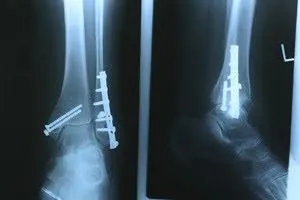

Dealing with Stress Fractures of the Foot and Ankle

Stress fractures occur in the foot and ankle when muscles in these areas weaken from too much or too little use. The feet and ankles then lose support when walking or running from the impact of the ground. Since there is no protection, the bones receive the full impact of each step. Stress on the feet can cause cracks to form in the bones, thus creating stress fractures.

What Are Stress Fractures?

Pain from the fractures occur in the area of the fractures and can be constant or intermittent. It will often cause sharp or dull pain with swelling and tenderness. Engaging in any kind of activity which involves high impact will aggravate pain.